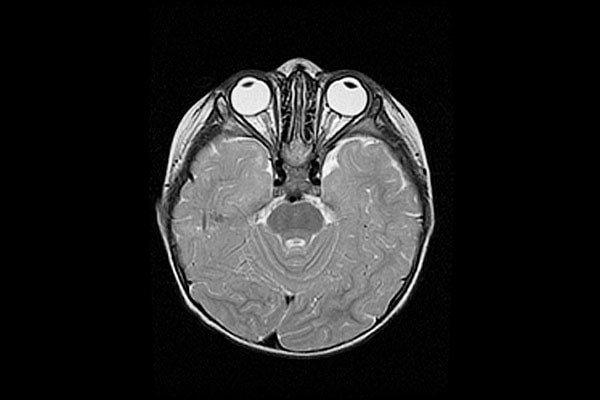

Scientists at U of T's Tanz Centre have shaped the course of neurodegenerative disease research (image by U of T News)